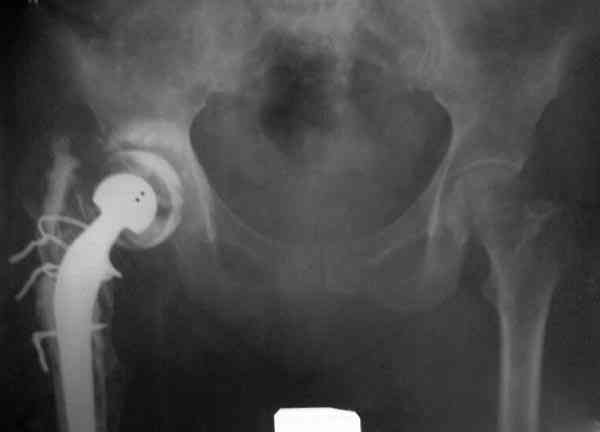

Повторная операция по удалению тотального протеза с irrigation&debridment, канал после очистки цемента обильно промыт и рассверлен римером.

Приготовлен цемент из расчета: Tobramycin 2.4 g (2 флакона), Vancomycin 2 млн (4 флакона) и 2 упаковки цемента с добавлением дополнительного флакона цементной жидкости.

После обработки ацетабулярного компонента, ещё в мягком цементе в полости вертлужной впадины головкой бедренного компонента сделана выемка для головки, чтобы свежий цемент не прилипал к головке. Головку бедренного компонента завернул обычной стерильной фольгой, которую после образования выемки отлепил от головки.

Для спейсера в бедро использовал старый длинный бедренний компонент меньшего диаметра, облепленный со всех сторон цементом с антибиотиком.

Наглухо ушитая рана с дренажом зажила первично, после чего с больной потерял контакт, и только недавно, через 8 лет я осмотрел её. Она без проблем нагружает на конечность и передвигается с помощью трости. От окончательной операции по реконструкции отказывается, довольная результатом.

и последние снимки.